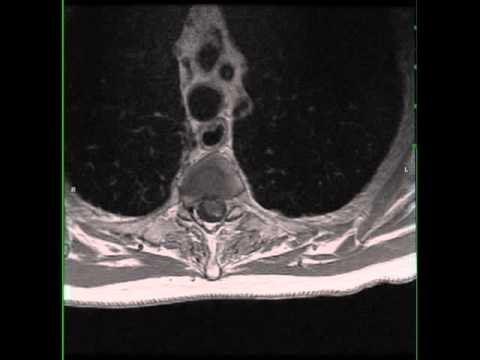

Hellow guys, Welcome to my website, and you are watching Posterior Transcallosal-Interforniceal Approach for Resection of a Pineoblastoma. and this vIdeo is uploaded by Barrow Neurological Institute at 2023-07-13T17:19:02-07:00. We are pramote this video only for entertainment and educational perpose only. So, I hop you like our website.